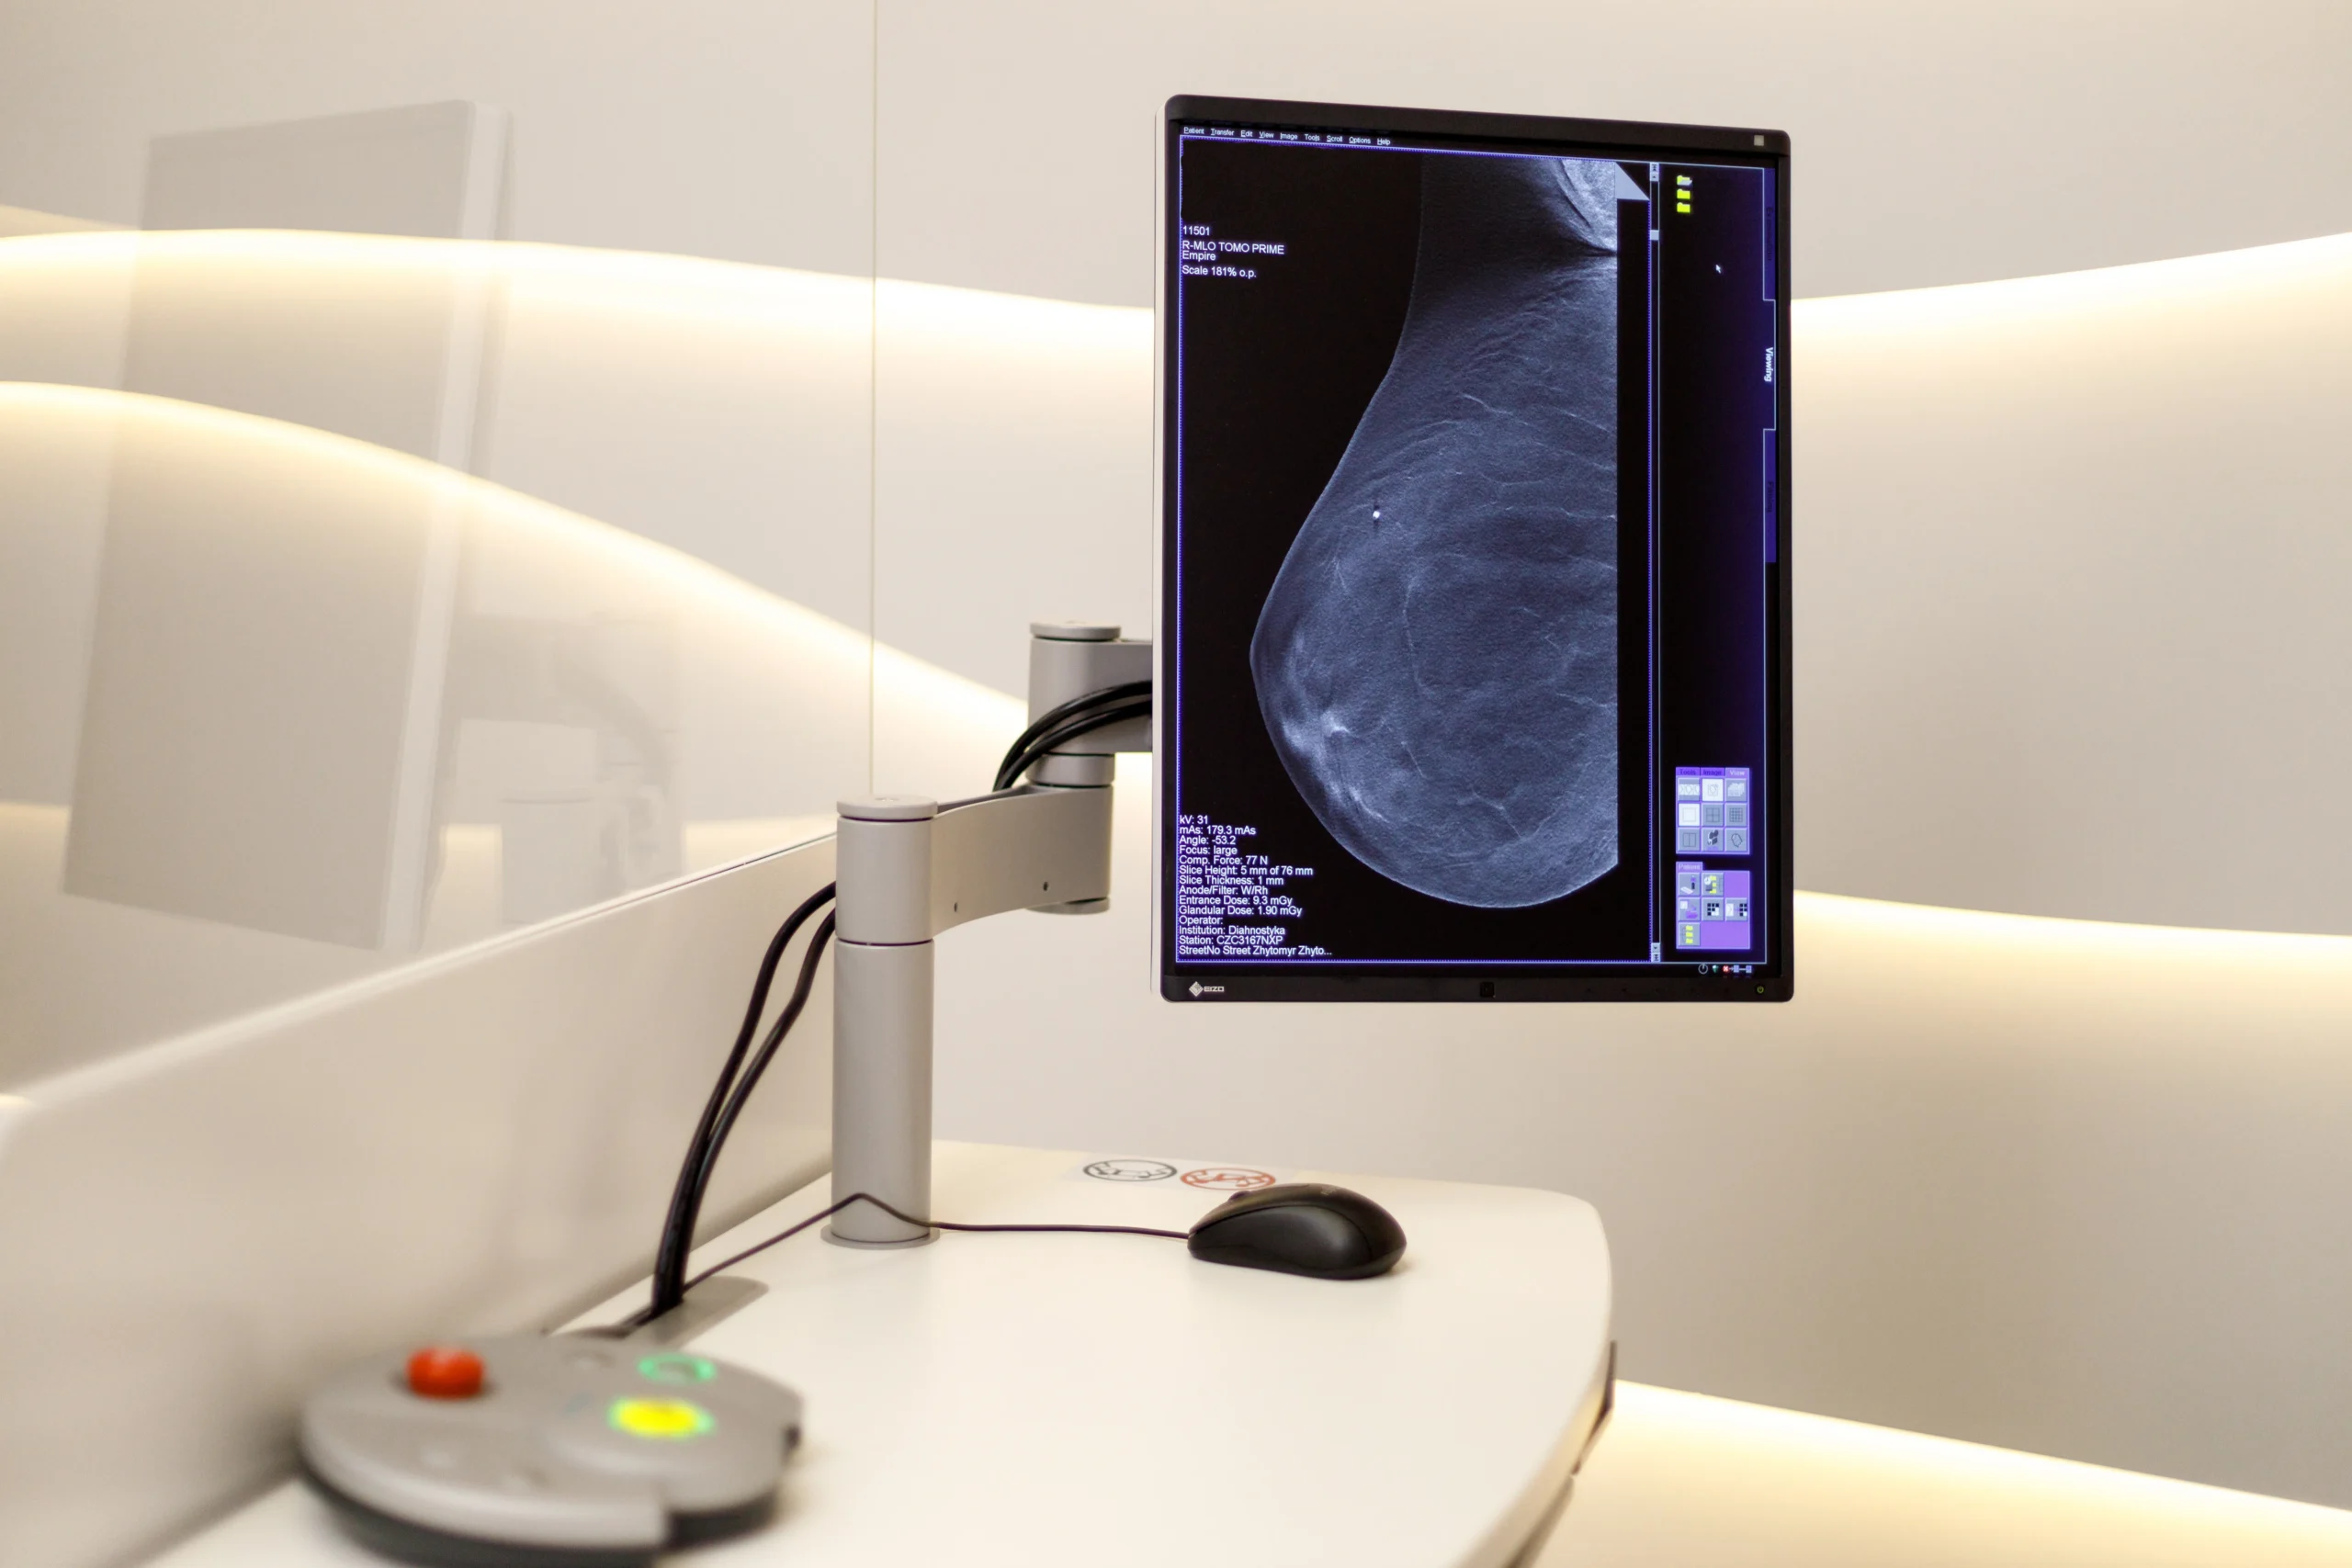

Обладнання

Мамограф з 3D томосинтезом Siemens Mammomat Revelation

Технології

🔹 використання ширококутного 3D томосинтезу (50°), що забезпечує неперевершену чіткість та деталізацію зображень;

🔹 застосування технології PRIME (Progressive Reconstruction of an Image Modality) для досягнення найнижчої дози опромінення без компромісів щодо якості;

🔹 високошвидкісний детектор, що значно скорочує час збору даних та зменшує ризик артефактів руху; -

Переваги

🔹 підвищення точності ранньої діагностики, що дозволяє виявляти патології на 30% раніше, особливо при дослідженні щільної тканини молочної залози;

🔹 високий рівень комфорту завдяки інноваційній системі Comfort Paddle та підігріву детектора (Bucky), що мінімізує неприємні відчуття;

🔹 скорочення загального часу обстеження до мінімуму, що робить процедуру швидкою та менш дискомфортною;

🔹 можливість проведення прицільної біопсії за допомогою інтегрованої системи InSpect, що забезпечує максимальну точність втручання;

🔹 інтеграція 2D та 3D зображень для лікаря (InSight 2D/3D), що підвищує якість аналізу та знижує ймовірність потреби у повторних знімках;